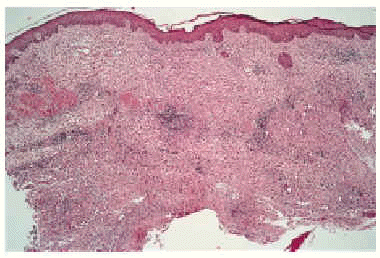

Hemos revisado desde el año 1995 hasta la actualidad las historias clínicas de pacientes con sospecha de infección cutánea por M. chelonae. Sólo los casos con cultivo positivo para este microorganismo fueron incluidos en esta revisión (tabla 1). Se trata de 6 pa-cientes, todas ellas mujeres, con edades comprendidas entre los 16 y 62 años (edad media: 24 años). Referían la aparición de 1 a 4 meses antes de la consulta de una o más lesiones de diferente morfología (pápulas, pústulas o nódulos) que en alguna ocasión se rompían y drenaban un material purulento (fig. 1). Las lesiones estaban localizadas de forma predominante en extremidades inferiores (fig. 2). Todas eran pacientes previamente sanas y no relataban un claro antecedente traumático, excepto la paciente número 6 que refirió el antecedente previo de una liposucción (fig. 3). Ninguna tenía fiebre, dolor o síntomas de enfermedad sistémica. Todas habían realizado tratamiento previo con cloxacilina sin respuesta. Con la exploración presentaban lesiones inflamatorias que se describen en la tabla 1. La mayoría eran lesiones nodulares de localización preferente en extremidades inferiores. El estudio anatomopatológico mostraba densos infiltrados inflamatorios de carácter agudo o crónico y abscesos o lesiones granulomatosas, sin obser- varse focos de necrosis caseosa (fig. 4). En ningún caso se encontraron bacilos ácido-alcohol resistentes en el interior de los granulomas mediante la tinción de Ziehl-Neelsen. En todos los casos se aisló una micobacteria de crecimiento rápido, que posteriormente fue tipificada como M. chelonae en medios de cultivo Coletsos y Lowenstein y en medio BACTEC MGIT 960, medio líquido, con sistema radiométrico para detectar el crecimiento. Las pruebas complementarias realizadas incluyeron un sistemático de sangre, bioquímica sanguínea, sistemático de orina, proteinograma, cuantificación de inmunoglobulinas, serología virus de la inmunodeficiencia humana (VIH), prueba de Mantoux y radiografía de tórax, con resultados normales o negativos. En todas las pacientes se instauró tratamiento con un régimen de antibióticos orales que incluía claritromicina en 5 de ellas, con buenos resultados. Excepto en una paciente que no acudió a revisión, en todas las demás no se encontraron lesiones nuevas y persistían sólo lesiones residuales.

Fig. 4.--Reacción inflamatoria granulomatosa confluente, con fenómenos de abscesificación en dermis profunda (hematoxilina-eosina, 40x.)